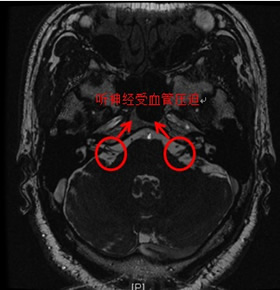

MRI上提示血管神经压迫 手术切口和骨窗开口图示 术中利用特氟龙棉垫解除神经血管压迫

林教授回忆说,4年前郑先生就诊时,通过MRI核磁共振检查就发现了他的听神经和脑血管关系密切,当时国外已有学者尝试通过手术治疗顽固性眩晕的例子,但因患者的对于手术的顾虑,当时并没有选择手术治疗。如今4年后再次回想起当时的诊断,又证明了当时对于难治性眩晕手术治疗的预见性。尽管如此,经检索,省内开展微血管减压治疗顽固性眩晕仍尚属首例。